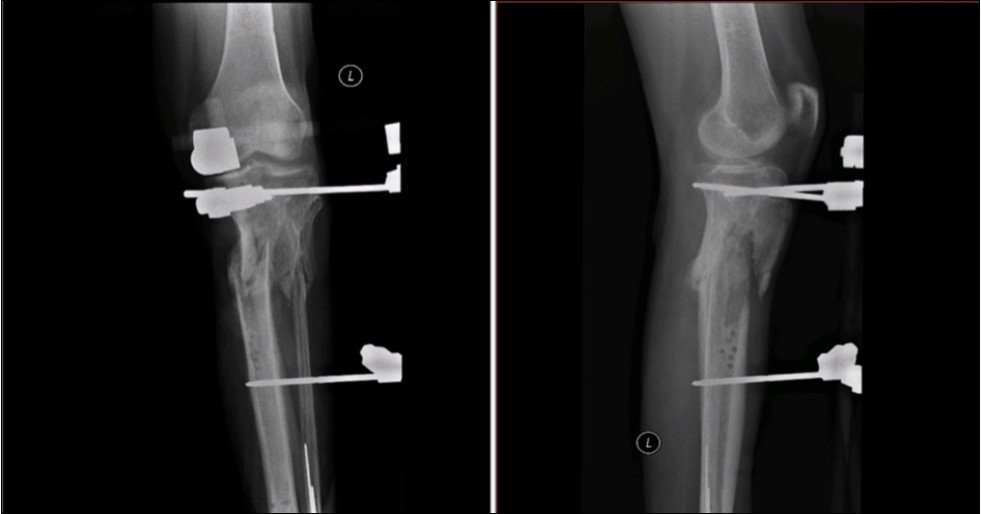

Case No.2 is about a man of 44 years old, where the injury caused by falling in ebrieta under the wheels of the bus. Primary acute treatment in the district hospital and then transferred to the Trauma Center of the Regional Hospital with open fracture of the tibia by Gustillo-Anderson IIIB 11. Extensive decollement of soft calf tissues up to the knee. Other diagnoses included the fracture of malleoli lateralis, acute hemorrhagic shock, traumatic shock, crash syndrome, acute alcohol intoxication.

Revision of limb perfusion and pulsation of marginal vessels. There was no detected injury of marginal vessels and nerves. MESS Absolute indication of amputation <7

Application of external fixation and Ki wires to stabilization of fragments.